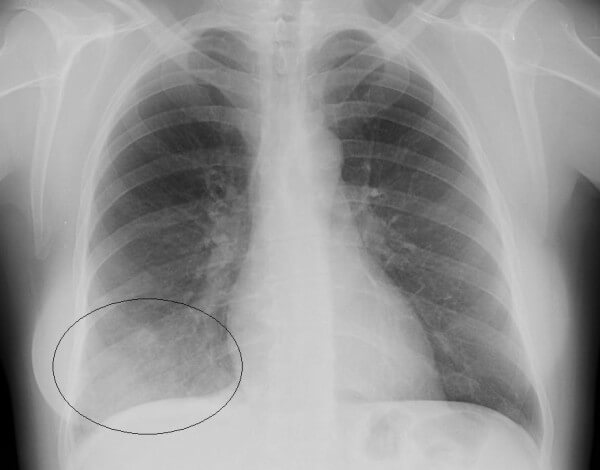

Сегментарная пневмония – воспаляется целый сегмент легкого. Данная форма пневмонии может осложниться ателектазом (спадением части легкого с полной потерей его воздушности. Сегментарная форма воспаления может быть проявлением длительной затяжной пневмонии, переходящей в легочный фиброз или осложненной локальным хроническим бронхитом. На рентген-снимках виден целый сегмент, пораженный воспалением.

На снимках видно, что воспалительный процесс локализуется лобарно или сублобарно (то есть поражается доля легкого) с вовлечением плевры. Легочный рисунок при этом изменяется, а легочные корни расширяются. Видны застои жидкости в плевральной полости. С течением болезни тени на снимках становятся темнее.

- Крупозная пневмония. Наблюдаются изменения нормального легочного рисунка, жидкость в полости плевры, признаки инфильтрации одной из долей легкого, расширение корней. По мере развития воспалительного процесса выраженность изменений и интенсивность окраски затемнений усиливается.